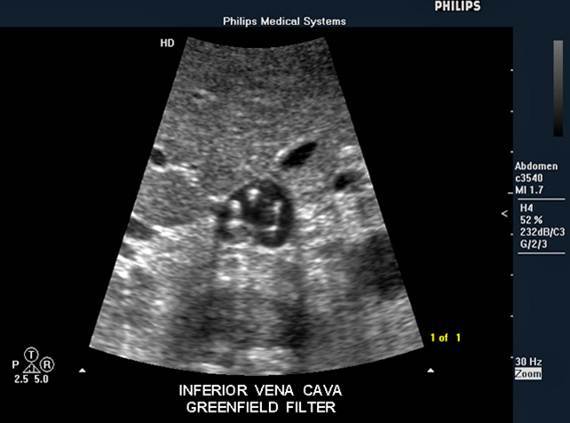

IVC Filters